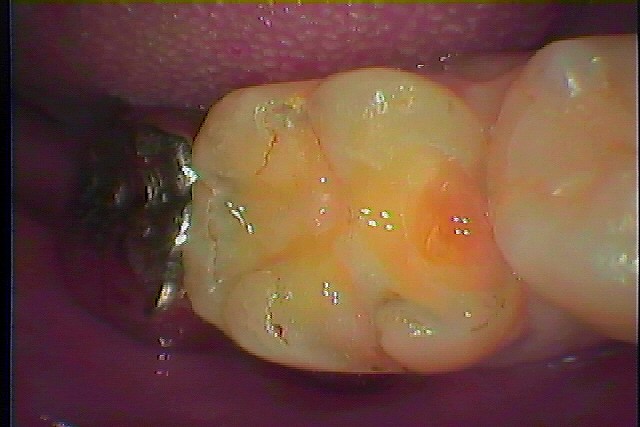

お知らせ|広島市安佐南区の歯科医院 > お知らせ トップ お知らせ・ブログ お知らせ スタッフブログ お知らせ お知らせ 2021/05/21 右上1番が矯正後、保定装置が取れ 数年で転出してきた 抜歯即時インプラント埋入へ お知らせ 2021/05/20 無歯顎の方にはインプラント診断として造影剤入りの人工レジンをもちいたステントを作成して、どの位置にインプラント埋入可能かを審査していきます お知らせ 2021/05/20 右下6,7番の銀歯から白いセラミックへやり変えていきます セラミックを用いた審美治療 お知らせ 2021/05/19 1か月半できれいに治癒してきました インプラント部の上部構造を建てていきます お知らせ 2021/05/19 右上5番が噛むと痛む 急に噛めなくなった診てほしい お知らせ 2021/05/18 右下6番の詰め物がかけた ほって置いたら痛くなりだした お知らせ 2021/05/18 右下6番のインプラント治療 欠損部にはインプラントを埋入しています お知らせ 2021/05/17 右下7番の銀歯を外していきます 手前はインプラント予定となっています お知らせ 2021/05/17 左上4番の銀歯外して虫歯治療 この銀歯の下に虫歯が存在しています お知らせ 2021/05/15 右下の6番が噛むと痛む 診てほしい 歯茎も腫れています << 1 2 3 4 5 … 212 213 214 215 216 … 485 486 487 488 489 >> Web診療予約 初めての方へ 選ばれ続ける理由 院内設備について 歯が痛いしみる一般歯科 歯がぐらぐらする歯周病 健康な歯を保ちたい予防歯科 子供の虫歯予防をしたい小児歯科 銀歯をセラミックに審美歯科 白い歯を目指しませんか?ホワイトニング 矯正専門医がいるので安心矯正歯科 抜けた歯を補いたいインプラント・入れ歯 医院案内 スタッフ紹介 メリィハウス歯科クリニックオフィシャルホームページ ラベンダー歯科クリニックオフィシャルホームページ お知らせ・ブログ ホーム 診療科目 一般歯科 歯周病治療 予防治療 小児歯科 審美治療 ホワイトニング 矯正歯科 入れ歯・インプラント マウスピース矯正 初めての方へ 院長・スタッフ 設備紹介 医院案内・アクセス メニューを閉じる